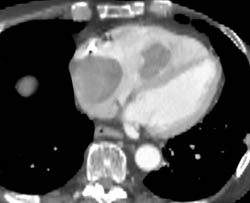

RCA With Multiple Calcified Plaques